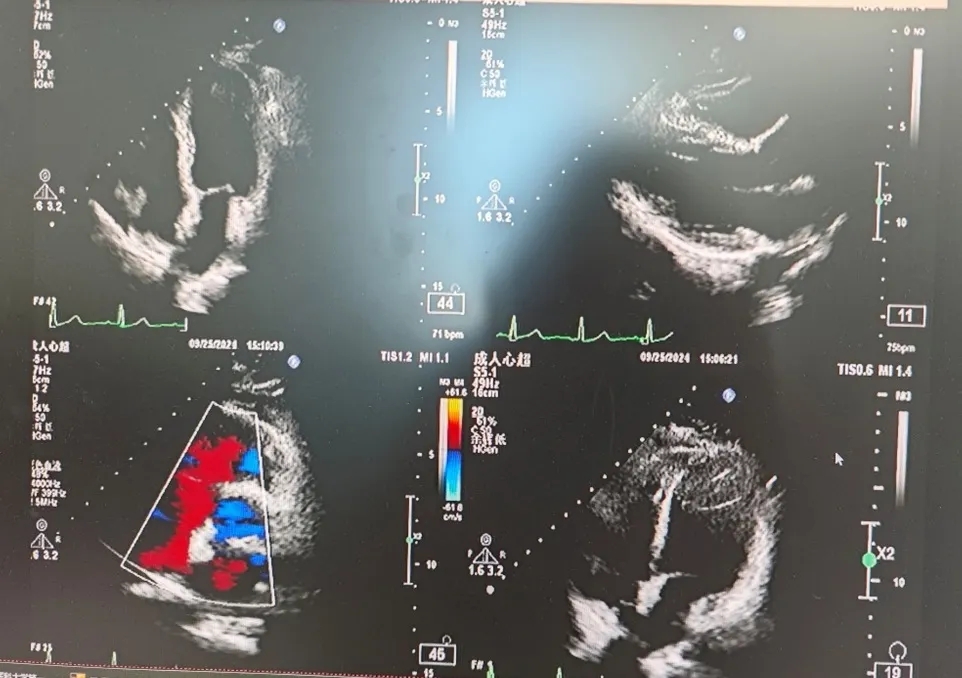

超声所见:经食管超声心动图+灰阶三维成像+彩色三维成像:卵圆孔未闭可吸收封堵器置入术后6个月:可吸收封堵器位置固定,未见残余分流,可吸收封堵器与房间隔自身组织贴合紧密,变薄,其回声与心肌组织回声接近,右房面可见封堵器的条状回声反射。

超声结论:经食管超声心动图+灰阶三维成像+彩色三维成像:卵圆孔未闭可吸收封堵器置入术后6个月:可吸收封堵器回声与心肌组织回声接近,未见残余分流。